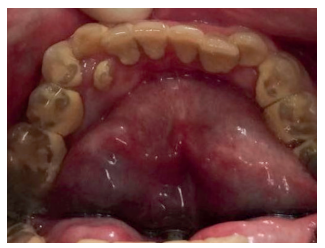

No es frecuente que estos pacientes presenten alteraciones a nivel dentario y gingival como en otros tipos de MPS, pero sí se ha observado una mayor incidencia de bruxismo. Además, pueden presentar dientes supernumerarios con la consiguiente maloclusión que, debido al deterioro del sistema nervioso central desde edades muy tempranas, no puede llevarse a cabo el control por el ortodoncista. En los casos en que, debido a inclusiones dentarias o dientes supernumerarios que provocan patología y se requiere su tratamiento quirúrgico, éste deberá llevarse a cabo bajo sedación25-27 (Figuras 6, 7 y 8).

Cuando comienzan el recambio dentario, se debe mantener continuas revisiones odontológicas, puesto que en estos casos existen problemas para la exfoliación de los dientes deciduos. Se pueden encontrar dientes supernumerarios e inclusiones dentarias, que serán extraídos por un especialista en quirófano bajo sedación profunda, debido a la alteración cognoscitiva importante que suelen presentar y/o hiperactividad en fases intermitentes39 (Figuras 9, 10 y 11).